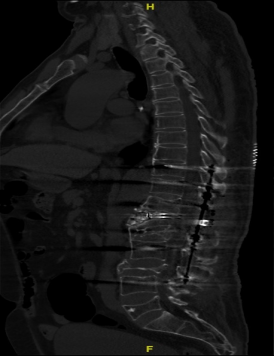

术前外观照术后CT影像:脊柱生理曲度恢复良好

经检查,赵伟教授发现该患者是一名弥漫性特发性骨肥厚疾病(dish病)患者,同时合并有胸12、腰1、腰3、腰5多节段陈旧性骨折,共同导致了胸腰段严重的后凸畸形、站立位失平衡。

根据患者的实际情况,赵伟教授团队组织麻醉科、手术室等多学科会诊,对王先生的病情进行全面的评估,并制定了合理的治疗方案,最终决定采用脊柱四级截骨矫形和椎管减压植骨融合内固定手术解决王先生的病痛。